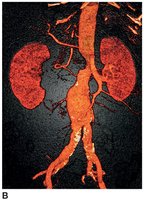

Aneurysm

An aneurysm is a localized dilation of a blood vessel, often in the abdominal aorta, which can rupture and cause severe bleeding.